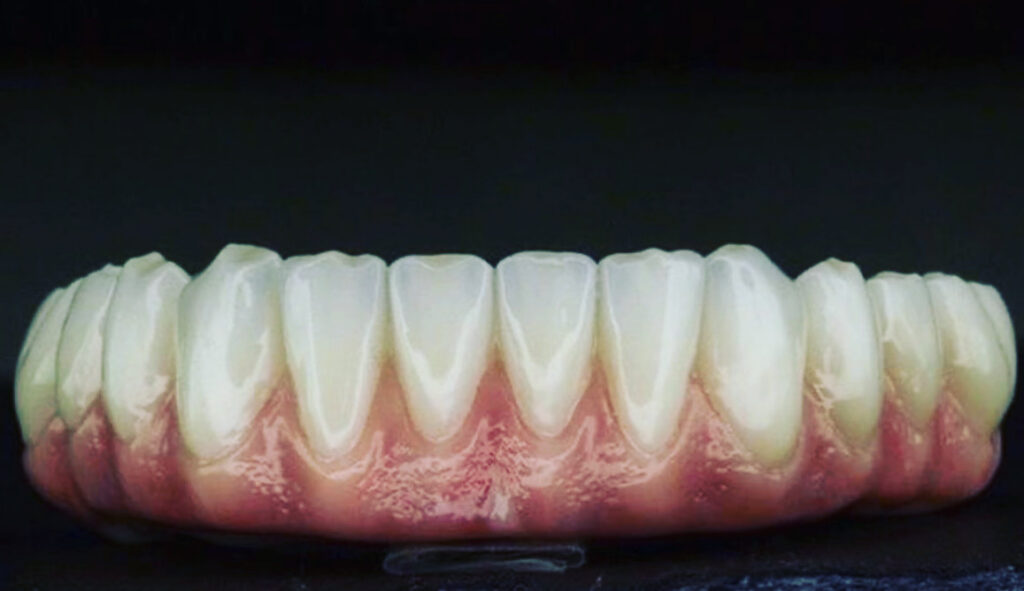

Gain confidence, live the life you want to live, eat the foods you want, and restore your full mouth with titanium implants that are masterfully crafted from zirconium and porcelain to restore a beautiful smile that’s strong enough to eat a steak and salad. Feel better and regain your confidence with our expert implant dentistry.

Take your life back by taking your smile back. Once your implants are in place, one of our implant dentists will attach a stunning, natural-looking restoration that looks and feels just like your natural teeth.

Our dental implants in Fort Worth offer the most natural feeling and looking solution there is when it comes to tooth restoration. You will be able to resume all of life’s activities, like eating and drinking, as you did before tooth loss. You will gain back your confidence, and the quality of your life will increase greatly.